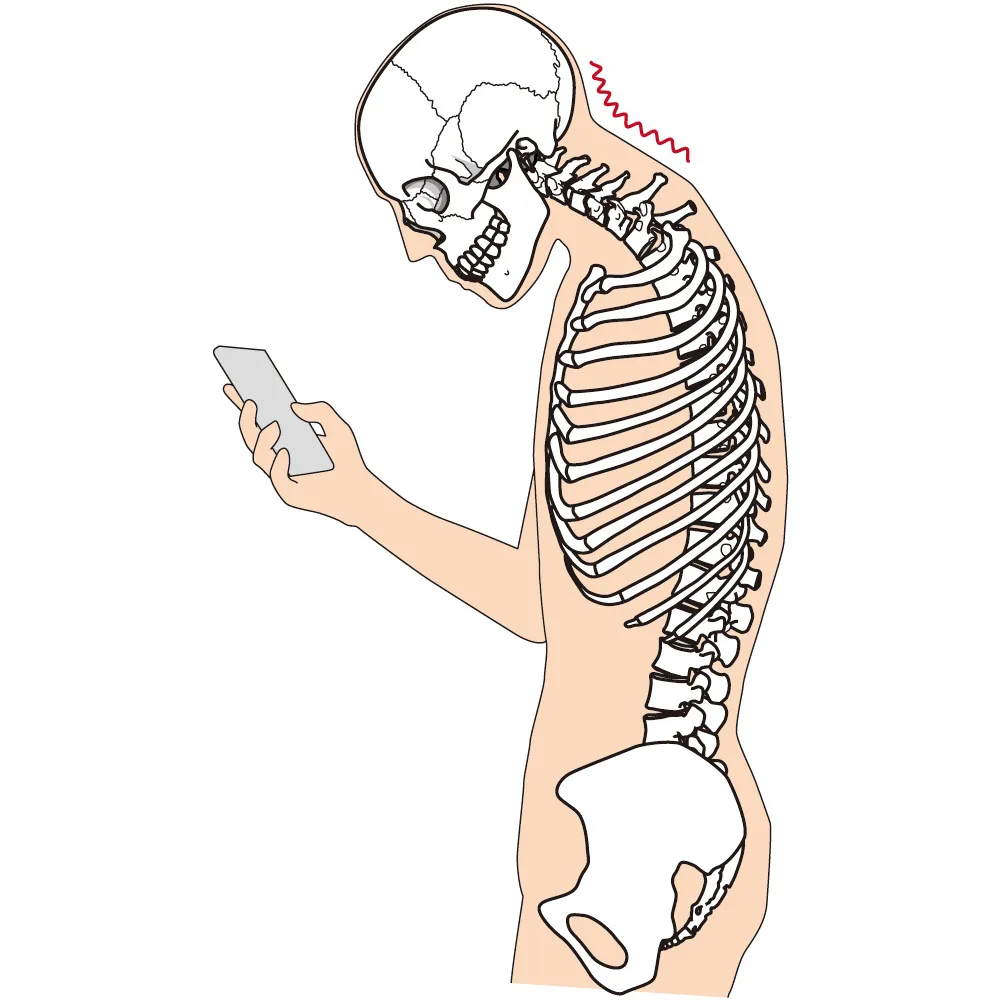

顎のズレは、体全体のバランスの崩れに直結します。

- 顎の位置がズレると、頭の重さをうまく支えられず姿勢が崩れる

- 姿勢の崩れは背骨や骨盤にまで影響し、全身のバランスを乱す

- 顎の突出により、首や腰に負担がかかる

顎がズレると「ストレートネック」「猫背」になりやすい

約5kgある頭部(500mlペットボトル10本分)の重さを、前方で支えることで常に筋肉が緊張する

NGバランス(悪い状態)

- 食いしばりなどにより、顎が前方に突出

- 頭蓋骨の付け根でズレが生じ、姿勢不良や不調を招く

- 筋肉や関節に持続的ストレス → 慢性疲労へ